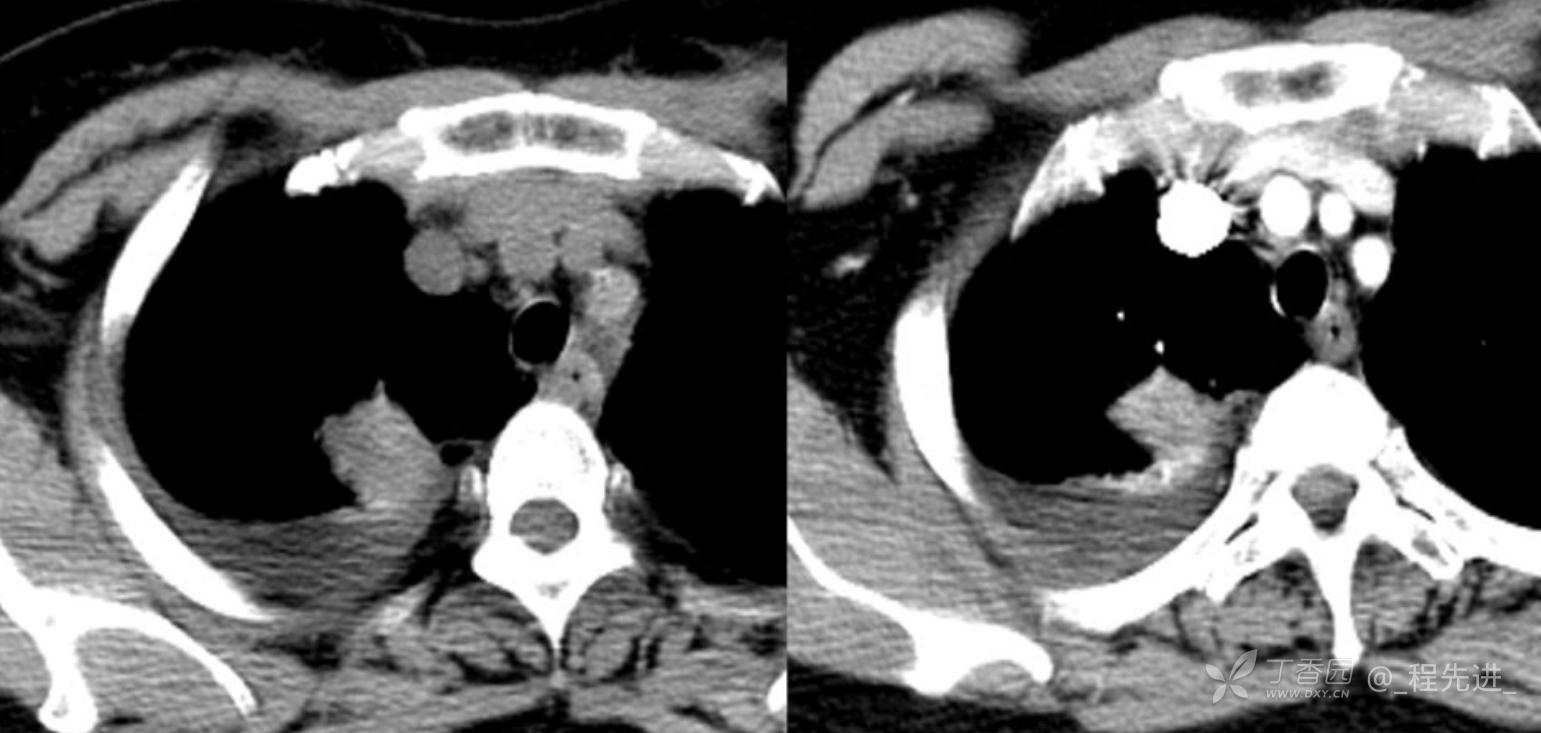

简要病史:乏力、纳差20余天,皮肤巩膜黄染半月偶有咳嗽,咳白痰,全身皮肤巩膜黄染。无咯血,无明显胸闷、胸痛,无明显气促,无发热及盗汗。精神欠佳,纳差,睡眠一般,二便正常